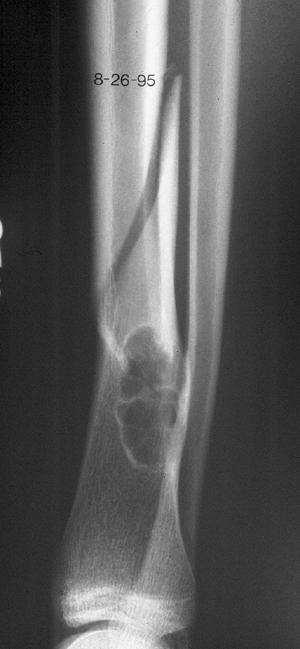

Figure 1-1 Pathologic fracture through unicameral bone cyst typically occurs without preceding pain.

Figure 1-2 Pathologic fracture through nonossifying fibroma typically occurs without preceding pain.

Figure 1-3 Pathologic fracture through an osteosarcoma is usually preceded by progressively worsening pain.P.9

Figure 1-4 Pathologic fracture through aggressive lesions such as this Ewing sarcoma is usually preceded by pain.

Figure 1-5 Pathologic fractures through giant cell tumors are usually preceded by pain, as was the case here.

Figure 1-6 Pathologic fractures through lesions created by metastatic carcinoma are often preceded by pain.-

“No” implies a latent lesion without

progressive destruction. Most of these lesions can be diagnosed by

radiograph alone without biopsy. This situation is most common in the

pediatric population. Many of these fractures may be allowed to heal

before addressing the lesion itself, unless there is the potential for

deformity. -

“Yes” implies a potentially aggressive or

malignant lesion. These lesions usually require a biopsy to establish

the diagnosis. This situation includes most malignant primary bone

tumors and metastatic lesions.